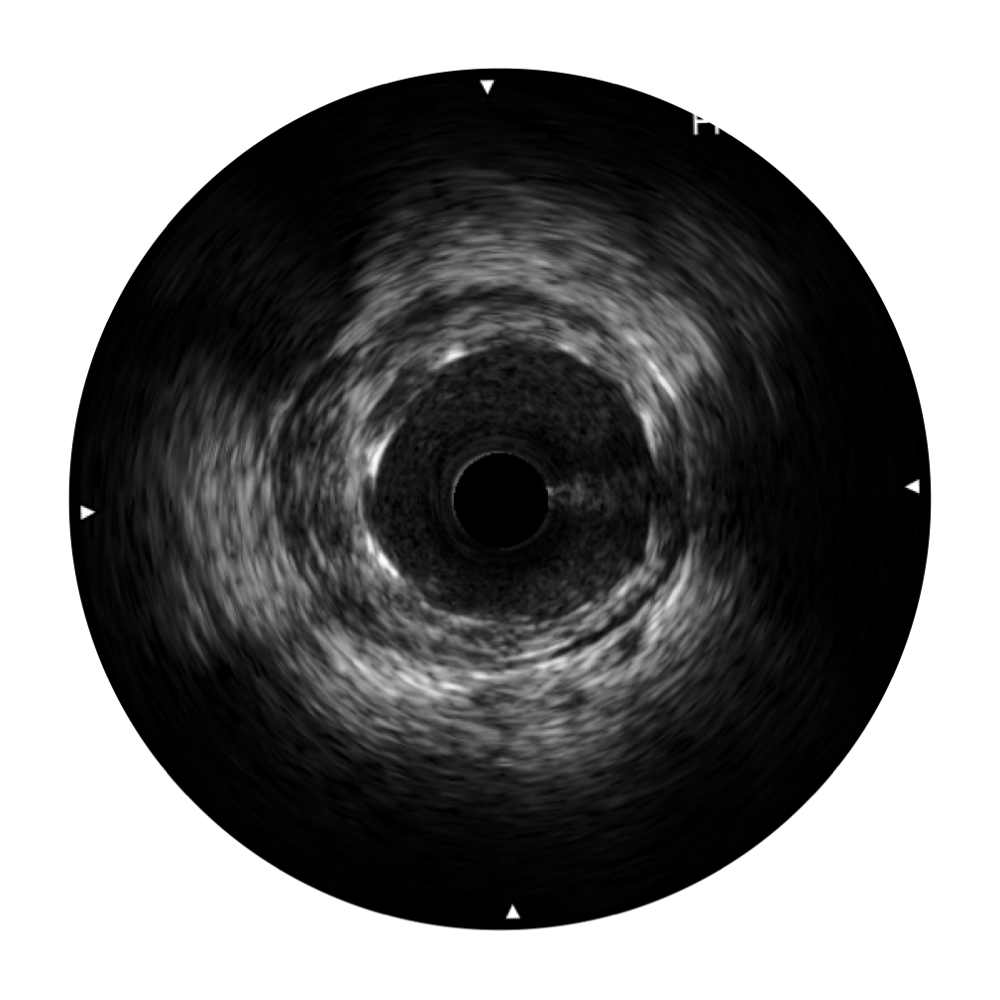

開立寬頻IVUS圖像

對比傳統(tǒng)IVUS導(dǎo)管成像,開立寬頻IVUS圖像的近場支架梁顯影更細(xì)膩,遠(yuǎn)場中膜外血管仍清晰可辨,兼顧遠(yuǎn)中近,兼顧分辨力與穿透深度